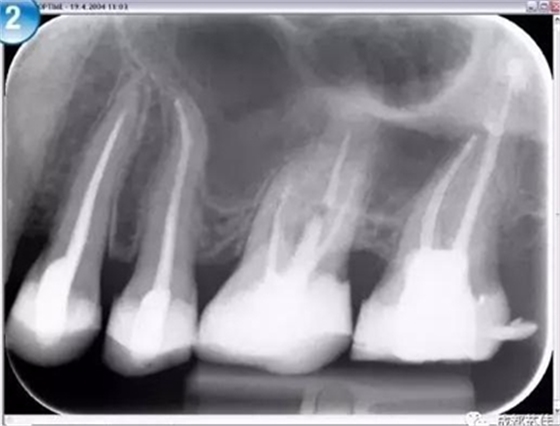

(2)超高空間分辨率及密度分辨率影像板完美的保證了成像質(zhì)量

Compass 2 使用最高敏感性和最智能的IP板讀取技術(shù)來獲取最高質(zhì)量的影像此外,Compass 2 允許減少曝光時間,從而減少欠曝和過曝。

空間分辨率最高可達(dá)16.7lp/mm,16位(65,636)的灰度,能夠可靠的分辨出D1級別的齲損及細(xì)小至ISO 06 級別的根管器械。

灰度值可自動調(diào)整,無需反復(fù)更改曝光設(shè)置也可獲得持續(xù)性的影像結(jié)果,影像讀取后只需微調(diào)即可獲得良好的影像減少過曝引起的偶然性。

(3)影像板感應(yīng)面積100%,可充分接收X光影像